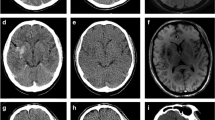

A diagnostic image quality was found in all 39 (100%) patients for both mixed images and iodine and VNC reconstructions from TwinSpiral DECT in both readers (Figs. 2 and 3).

A standard native non-contrast computed tomography (CT) mixed image from TwinSpiral dual-energy CT shows a hyperdensity in the Sylvian cortex on the right side (blue arrow) in an acute ischemic stroke patient after endovascular thrombectomy (a). The hyperdensity is also seen in the same location on the virtual non-contrast (VNC) image (b). No hyperdensity is seen on the iodine map (c). Follow-up magnetic resonance image (MRI) (d) showing a susceptibility artifact (blue arrow) on a susceptibility-weighted imaging (SWI) corresponding to the hyperdense area seen on the standard mixed and VNC images, but not on the iodine map, thus proving an intracerebral hemorrhage

A hyperdensity is seen in the left basal ganglia (blue arrow) on a standard non-contrast mixed image from TwinSpiral dual-energy CT image in an acute ischemic stroke patient after endovascular thrombectomy (a). No hyperdensity is seen in the same location on the VNC image (b). Hyperdensity is seen on the iodine map (c). Follow-up non-contrast CT (d) showing no hyperdensity at the corresponding location (blue arrow), thus indicating the contrast extravasation resorbed in follow-up imaging